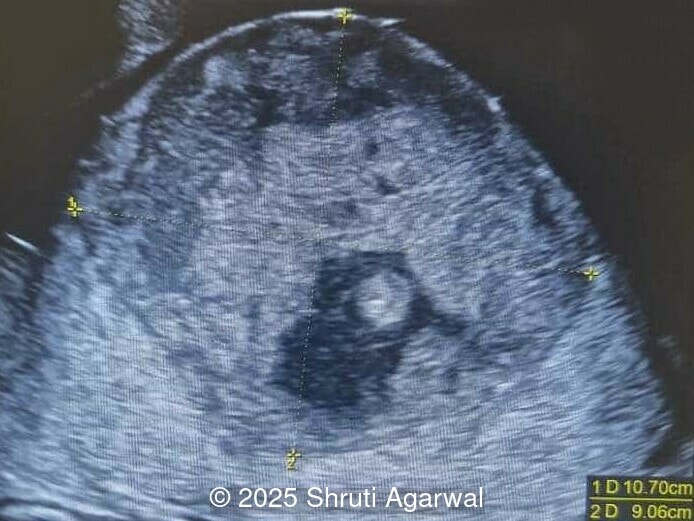

We present a case of fetal anemia due to a giant chorangioma.

- Image 1,2: Large placental tumor is identified with internal vascularity

Prenatal diagnosis depends on ultrasound, however, chorangioma can cause an increase in maternal serum alpha-fetoprotein [3]. Ultrasound examination reveals a hypo- or hyperechoic, well-circumscribed mass, which is usually located underneath the chorionic plate near the umbilical cord insertion, and often protrudes into the amniotic cavity. Color Doppler demonstrates large vascular channels around and within the tumor [6,9]. In cases of giant chorangiomas, echocardiography should be performed to assess cardiac function and measure fetal middle cerebral artery peak systolic velocity for diagnosis of fetal anemia. Regular ultrasounds with Doppler studies are used to monitor tumor size, fetal growth, amniotic fluid volume, and signs of fetal anemia or heart failure. The frequency of exams is based on tumor size and associated complications. With small tumors, assessment may occur every 3-4 weeks, whereas in large tumors, the ultrasound scan may be done every 1-2 weeks [3]. These regular assessments can diagnose conditions that require intervention, such as polyhydramnios, hydrops, or hemolytic anemia.